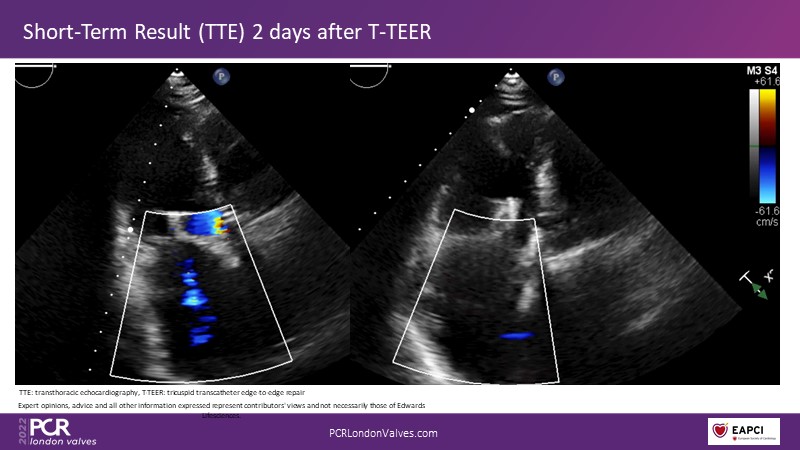

This innovative session takes you through the patient selection and anatomical characteristics when selecting amongst the different transcatheter options to treat tricuspid regurgitation, followed by a recorded demonstration using the PASCAL Precision repair system.